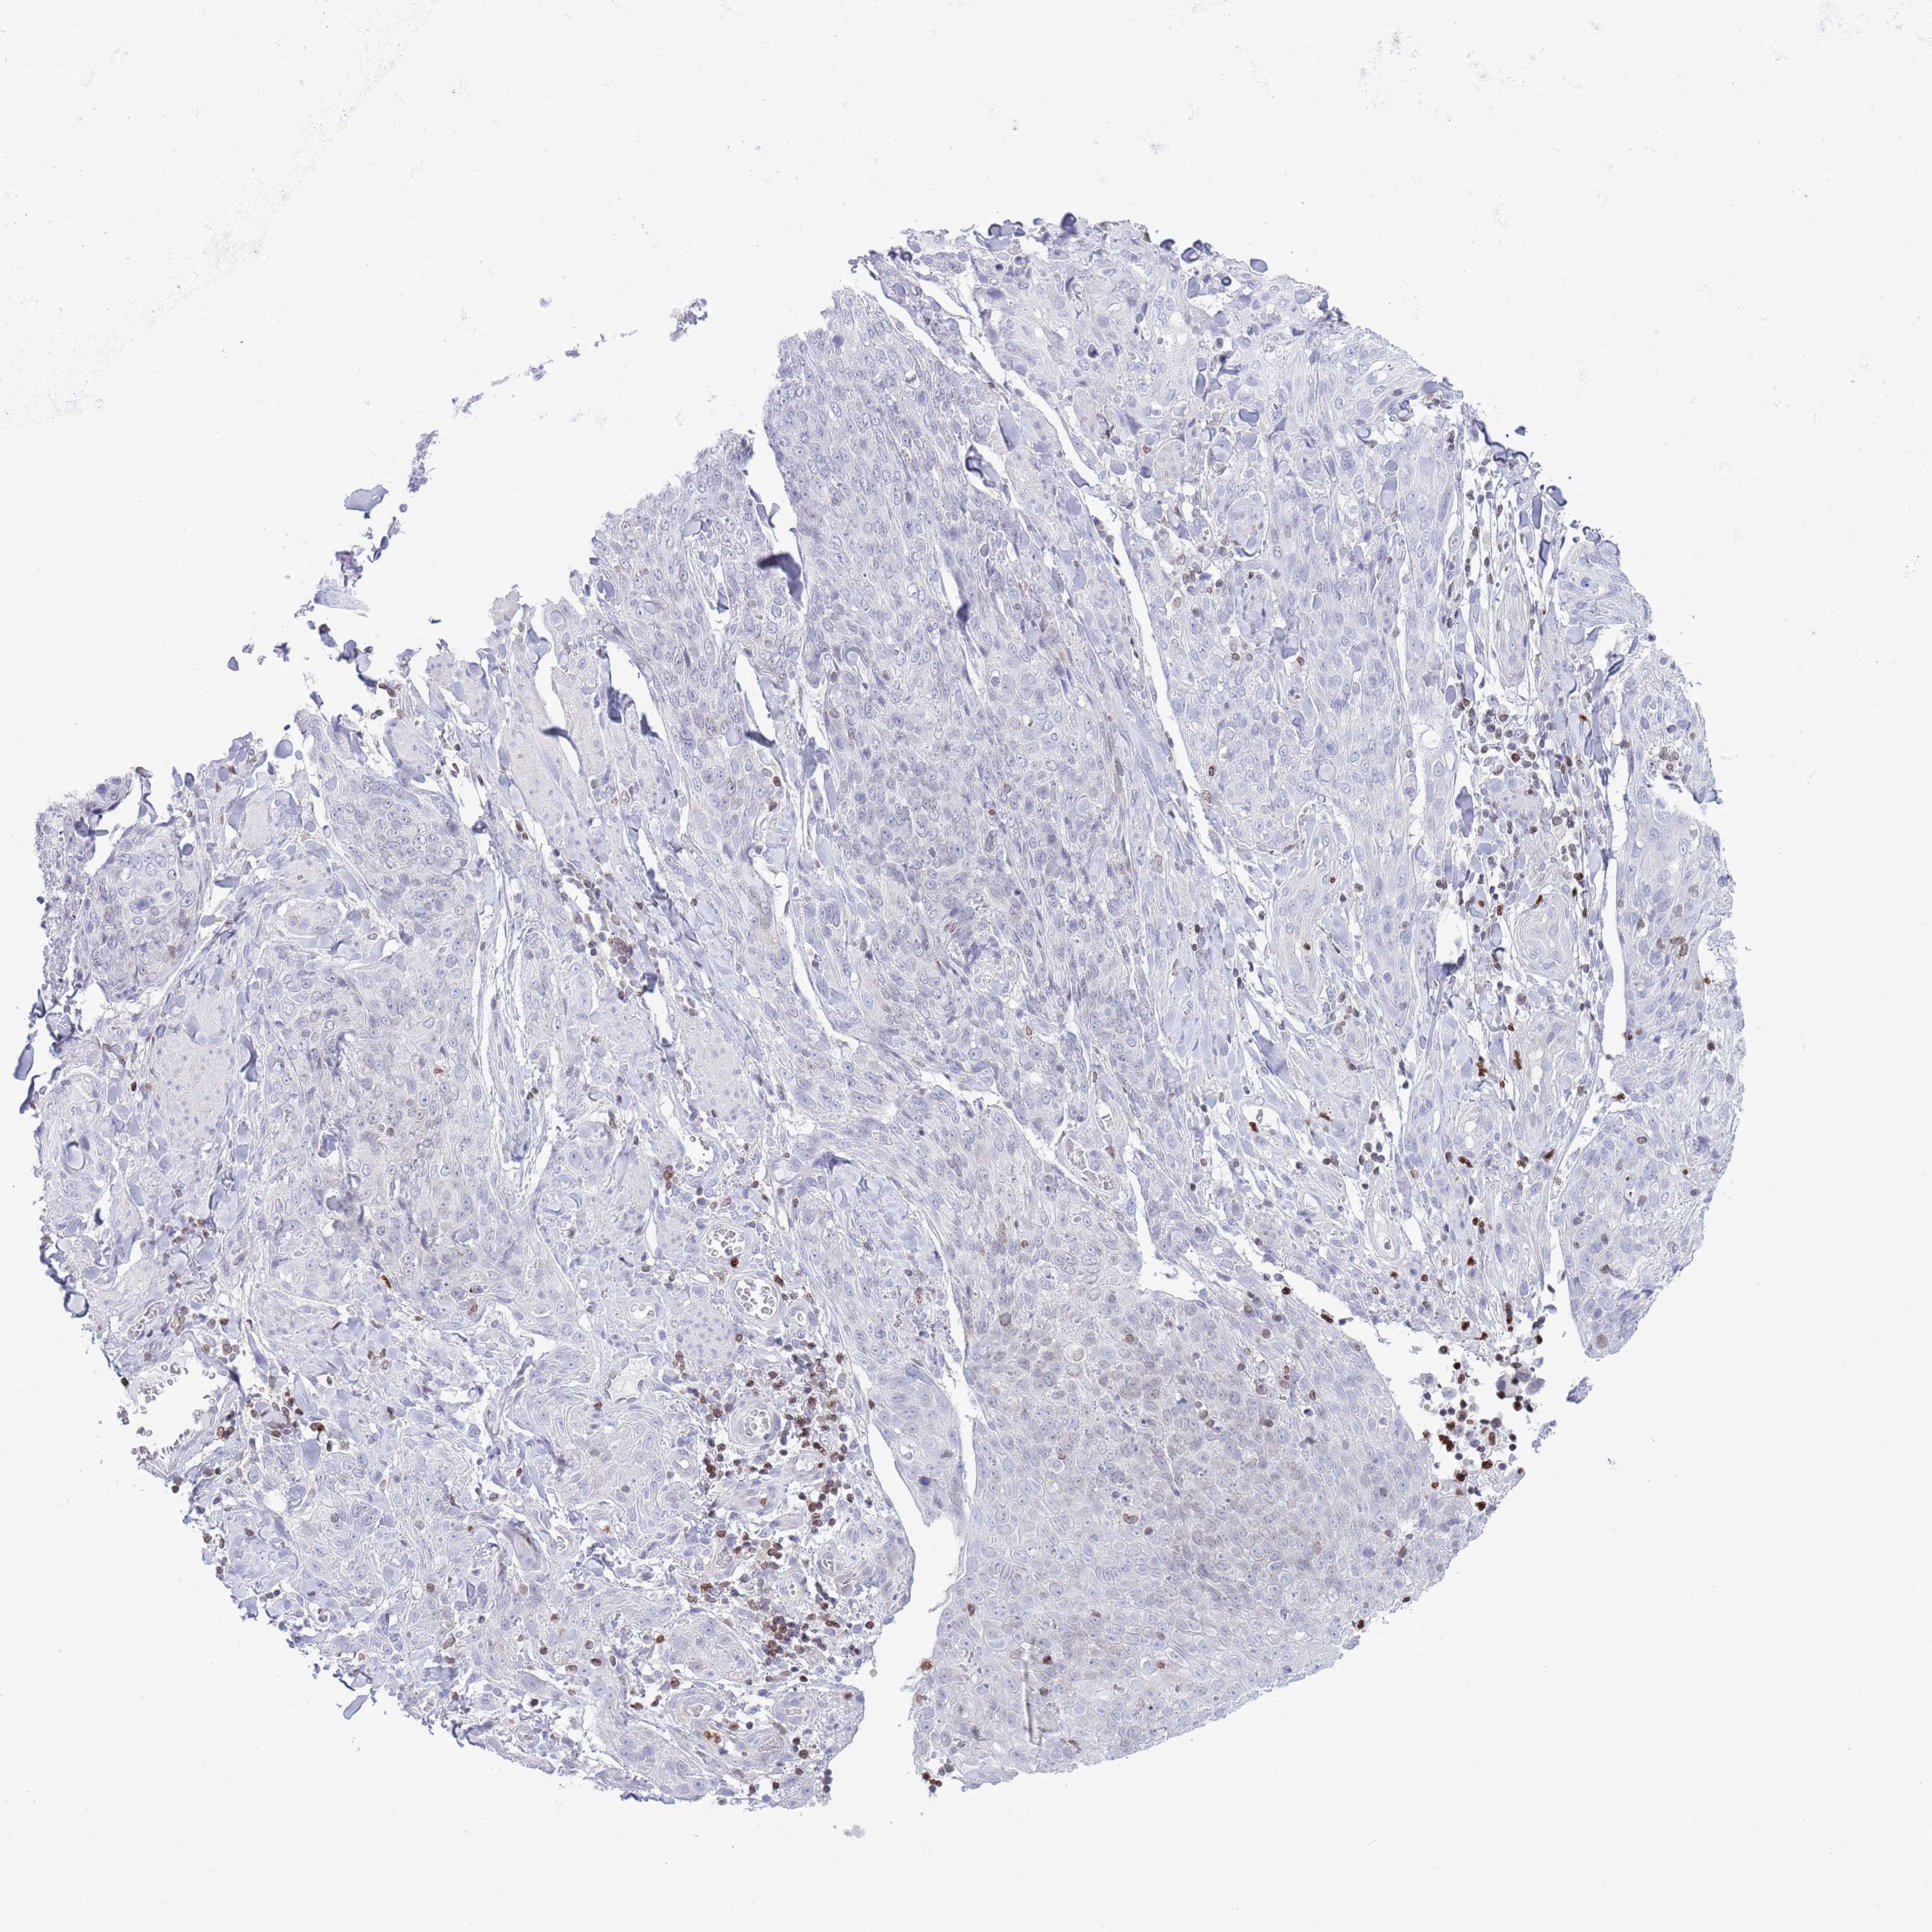

Basal cell and squamous cell cancer

SKIN CANCER - Protein expressioni

A mouse-over function shows sample information and annotation data. Click on an image to view it in a full screen mode. Samples can be filtered based on level of antibody staining by selecting one or several of the following categories: high, medium, low and not detected. The assay and annotation is described here.

Antibody stainingi

Antibody staining in the annotated cell types in the current human tissue is reported as not detected, low, medium, or high, based on conventional immunohistochemistry profiling in selected tissues. This score is based on the combination of the staining intensity and fraction of stained cells.

Each image is clickable and will lead to virtual microscopy that enables deeper exploration of all samples and also displays staining intensity scores, fraction scores and subcellular localization as well as patient and tissue information for each sample.

Antibody HPA062236

Staining

Not detected

Negative

None

Squamous cell carcinoma, NOS

Squamous cell carcinoma, metastatic, NOS